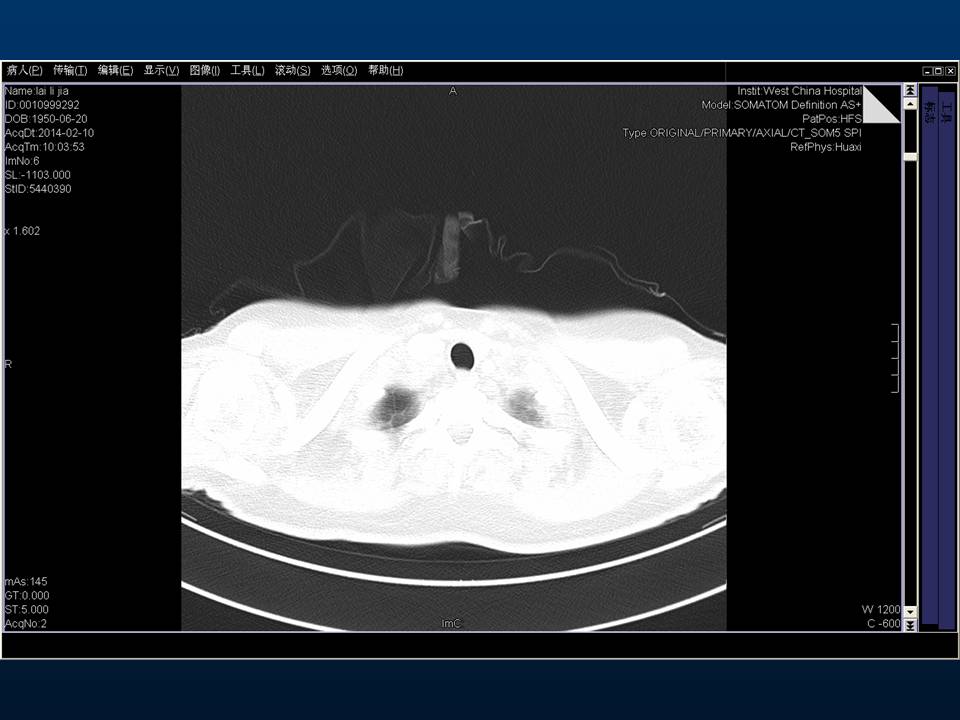

心房颤动(扑动)与“心衰”一例特殊病例报道